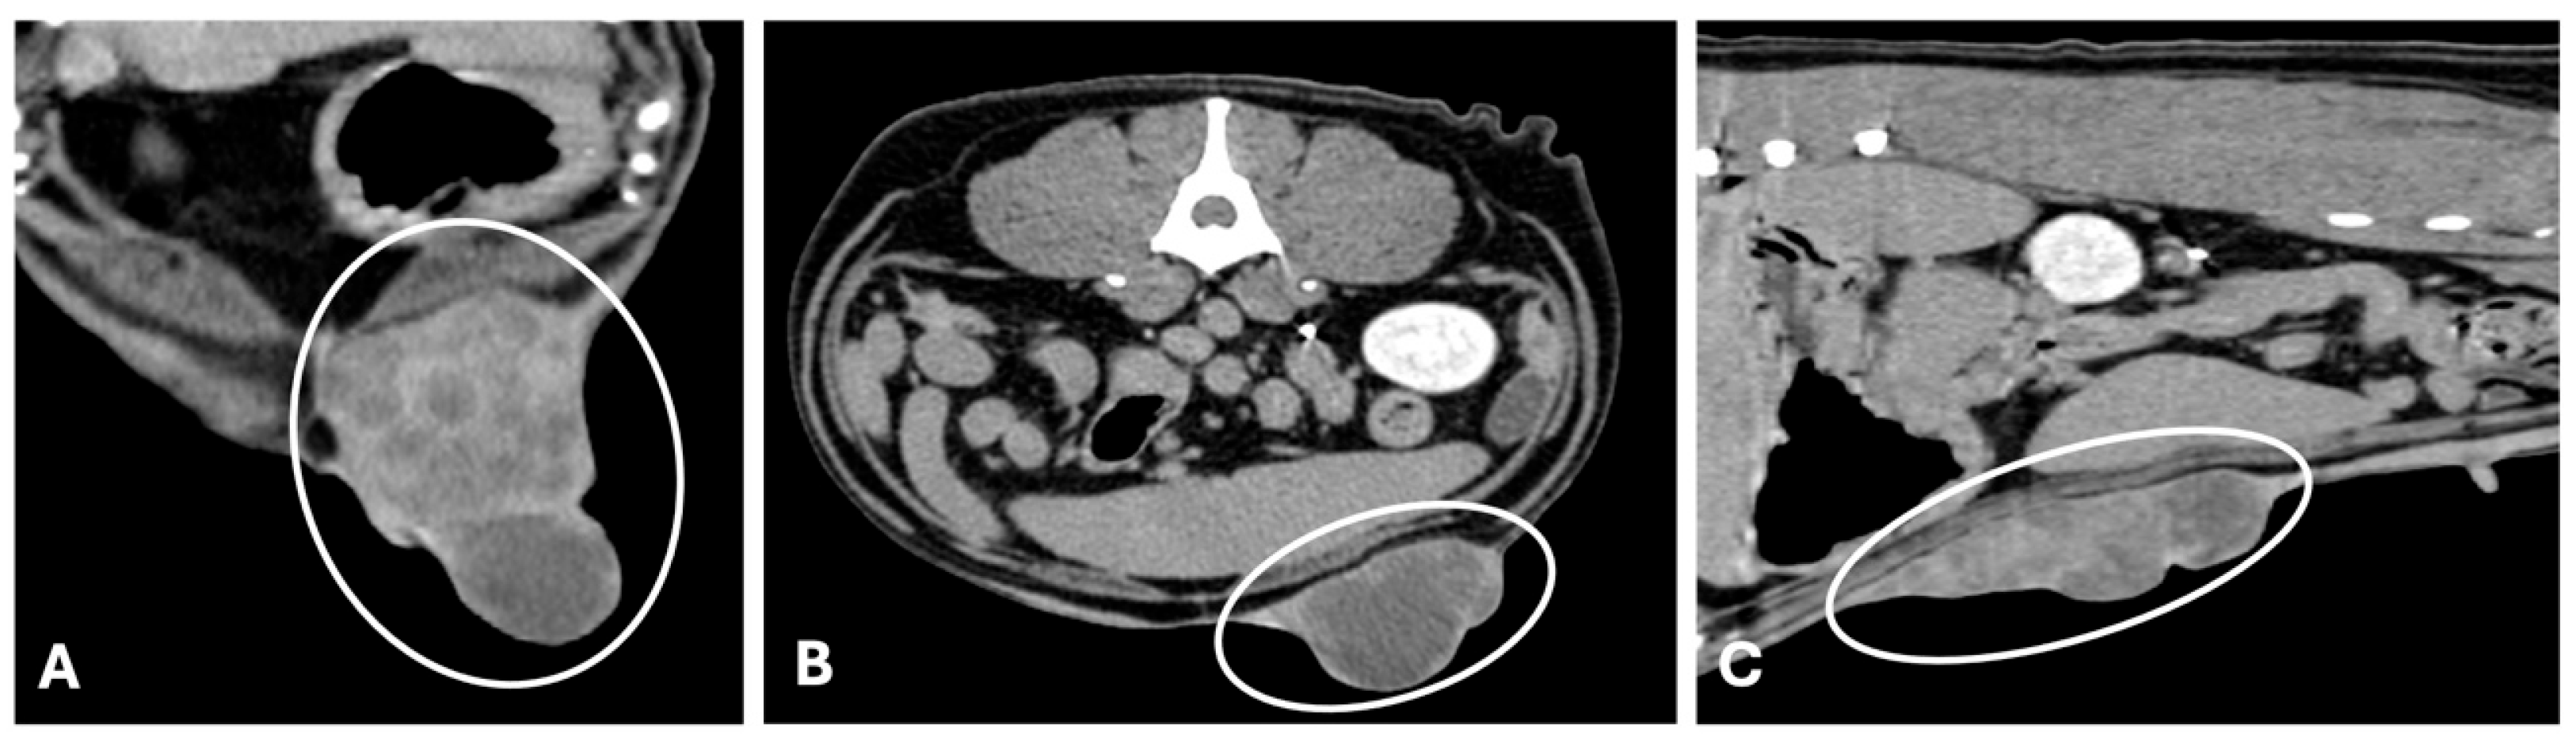

3.2. Computed Tomography

- Kim, S.; Kwon, K.; Choi, H.; Lee, Y. Evaluation of Mammary Gland Calcification in Dogs: Radiography and Computed Tomography. J. Anim. Reprod. Biotechnol. 2017, 32, 183–192. [Google Scholar] [CrossRef]

- Otoni, C.C.; Rahal, S.C.; Vulcano, L.C.; Ribeiro, S.M.; Hette, K.; Giordano, T.; Doiche, D.P.; Amorim, R.L. Survey Radiography and Computerized Tomography Imaging of the Thorax in Female Dogs with Mammary Tumors. Acta Vet. Scand. 2010, 52, 20. [Google Scholar] [CrossRef]

- Fonseca Pinto, A.C.B.C.; Iwasaki, M.; Figueiredo, C.M.; Cortopassi, S.R.G.; Sterman, F.d.A. Tomografia Computadorizada do Tórax de Cadelas Portadoras de Neoplasias Malignas. II—Avaliação dos Campos Pulmonares. Braz. J. Vet. Res. Anim. Sci. 2007, 44, 174–182. [Google Scholar] [CrossRef]

- Fields, E.L.; Robertson, I.D.; Osborne, J.A.; Brown, J.C. Comparison of Abdominal Computed Tomography and Abdominal Ultrasound in Sedated Dogs. Vet. Radiol. Ultrasound 2012, 53, 513–517. [Google Scholar] [CrossRef] [PubMed]